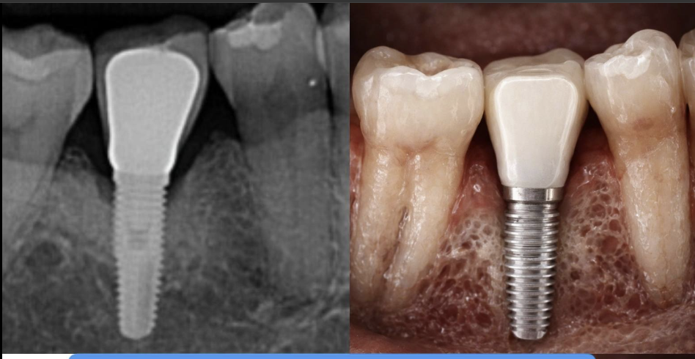

Move beyond 2D radiographs. Learn how to use CBCT to detect proximal, occlusal, and root caries with greater precision, and understand the limitations and benefits of 3D imaging for caries.

Detect periapical pathology, complex root anatomy, and vertical root fractures that are invisible on 2D films. Learn the CBCT criteria that change treatment decisions and improve outcomes.